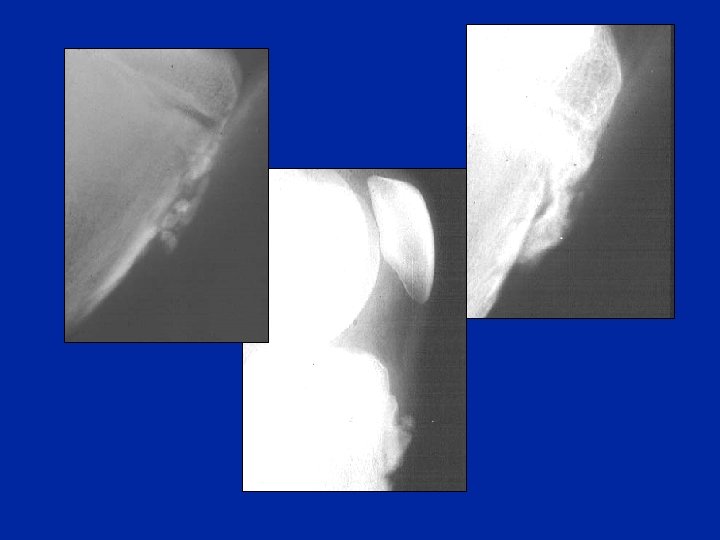

Osgood: radiología • • Contorno “impreciso” del rostro epifisiario Aspecto desgastado de la epífisis sub-condral Cuerpos extraños intra-tendinosos Fragmentación de la zona de inserción del tendón, correspondiente a los microarrancamientos ósteo-periósticos. • Desplazamiento anterior de la extremidad rostral de la epífisis • Los arrancamientos completos son raros • RMN: Edema del tendón rotuliano

Aspectos radiológicos (de perfil) rayos blandos

Aspectos clínicos y radiográficos • Sintomatología parecida al Osgood • Posible confusión con un síndrome rotuliano • Dolor preciso a la compresión de la punta de la rótula. • Radiografía: pequeñas modificaciones de la punta de la rótula y a veces se observa un pequeño fragmento desprendido.